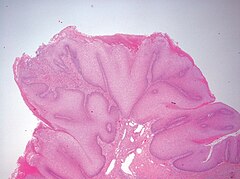

Figure 1

Perianal warty papules.

A provisional diagnosis of verrucous epidermal naevus was made and a punch biopsy specimen was obtained. Histological examination corroborated the clinical diagnosis by showing hyperkeratosis, acanthosis, and papillomatosis without any evidence of vacuolar change in the keratinocytes or any dermal pathology.